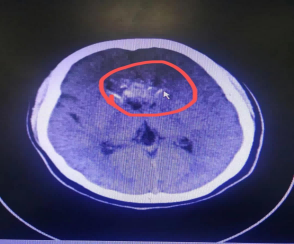

李女士因“头痛2天”到我院神经外科就诊,头颅CT回示:颅内占位,考虑室管膜瘤待排。

术前头颅CT显示颅内占位